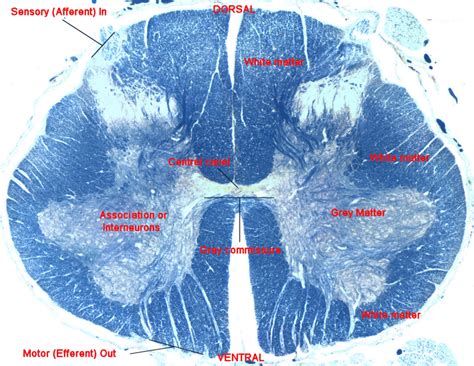

We did not find results for: spinal cord cross section labeled. Cross section spinal cord diagram labeled.